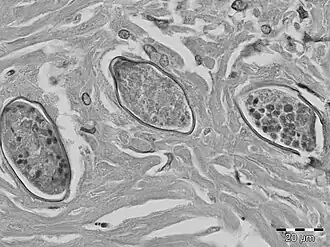

Schistosoma malayensis é um verme achatado parasita do filo Platyhelminthes, classe Trematoda. Habita a Malásia.